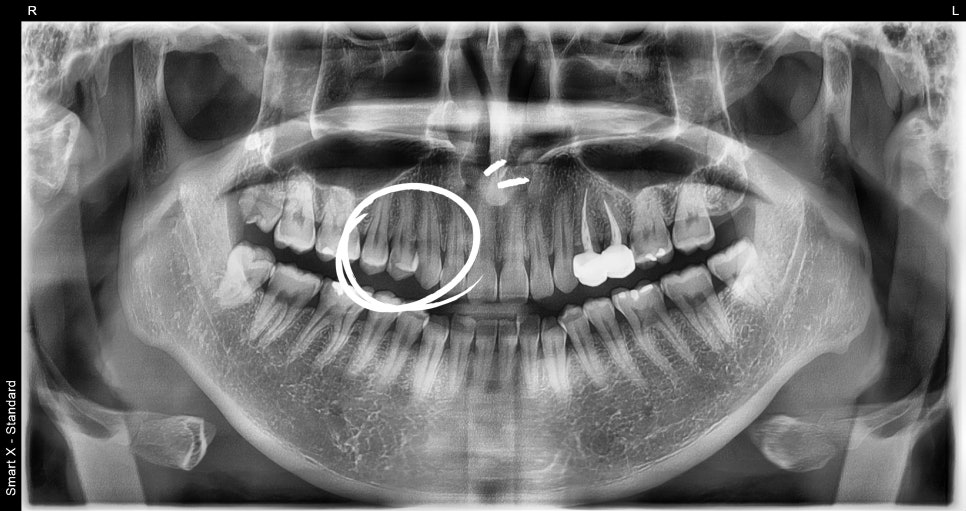

환자분 처음 내원당시

어금니가 꺠지면서 씹을 때 찌릿하고 쑤시는 느낌이 나요

치과에서 찍은 사진과 엑스레이를 확인해보니,

깨진 틈으로 세균이 들어가

신경이 이미 많이 손상된 상태였습니다.